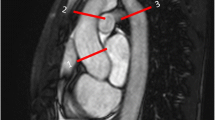

The image analysis consisted of two parts to determine aortic PWV and the WSS. In order to obtain the PWV, the acquired proximal PWV and diaphragmatic PWV images firstly were analysed using the in-house developed software MASS (LUMC). This software was used to perform velocity mapping and to measure the length of both aortic segments on a multislice survey of the aorta. Lastly, these quantifications were imported into an in-house developed MATLAB-based application to determine the PWV of the proximal and descending aorta, using the foot-to-foot method (Fig. 1). In all subjects, the PWV image analysis was performed by a single observer (IN) with over 3-year experience in cardiovascular MRI, supervised by an experienced researcher (JW) with over 20 years’ experience in cardiovascular MRI. Additionally, the PWV ratio was also derived from these values, defined as the descending aorta PWV divided by the proximal aortic PWV. This PWV quantification method was previously validated and described in more detail by Grotenhuis et al. [23].

Example of a patient aortic coarctation and tricuspid aortic valve without reobstruction. a Pulse wave velocity segments (Seg.): 1, proximal aorta; 2, descending aorta. b Wall shear stress segments: Asc AO, ascending aorta; Arch, aortic arch; Desc AO, descending aorta. c Three-dimensional magnitude wall shear stress map

From 4D flow MRI, the WSS was determined using CAAS MR Solutions v5.0 (Pie Medical Imaging, Maastricht, The Netherlands), assuming a constant blood viscosity of 4 mPa s. This software was used to compute the WSS over five time phases and three consecutive aortic segments (Fig. 1): the aortic root plus the ascending aorta, the aortic arch, and the descending aorta (respectively; from the aortic valve to the brachiocephalic artery, from the brachiocephalic artery up and including the left subclavian artery, and from the subclavian artery to the abdominal descending aorta at the level of measurement of the diaphragmatic PWV). This was accomplished by firstly segmenting the aorta on a combined weighted magnitude and velocity image for all five available time phases, incorporating only the aorta and excluding the main branches (e.g., the subclavian and carotid arteries). Secondly, the anatomical segmentation planes were manually placed and imported perpendicular to the aortic wall. From proximally to distally on the aorta, these planes were positioned at the aortic valve, proximally against the brachiocephalic artery, distally against the subclavian artery, and 10 cm caudal below the diaphragm. Thirdly, for the five available time phases and each anatomical segment, the maximal WSS was exported from CAAS. Lastly, these maxima over the five time phases were used to determine the peak WSS for each anatomical segment over all five time phases. The WSS image analysis was performed by a single observer (IN) in all patients. The applied method to determine the WSS in the five systolic time phases was previously described and validated on the reproducibility by van der Palen et al. [24].